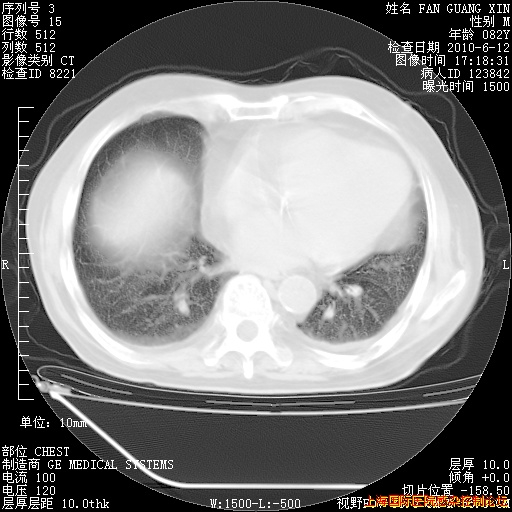

补发6月12日肺部CT肺窗

6月12日肺窗